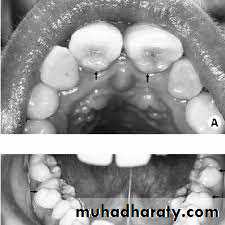

2- Presence of supernumerary teeth

3- Ectopic eruption of teeth

5- Prolonged retention of primary teeth

9- Palisading maxillary molars.UNIVERSITY OF MOSUL

• 5- Transposed teeth.• 6- Uneven resorption of deciduous roots.

• 7- Prolonged retention of primary teeth.